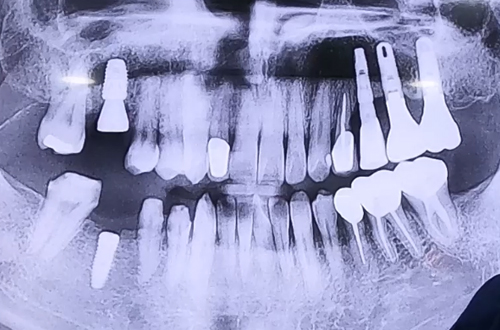

BEFORE

깊은 충치로 인해 오른쪽 어금니가 깨져서 복원할 수 없어

발치 후 즉시 임플란트를 진행한 사례입니다.

상한 치아를 빼시고 그 자리에 바로 임플란트를 심은 뒤,

빈 공간을 뼈이식으로 단단히 채워주고 보호를 위해 덮개를 덮어 마무리해 드렸습니다.

그 외 주변 뼈들은 굉장히 좋으셔서 임플란트 진행이 어렵지는 않았어요~

그 외에 다른 치아들도 전반적으로 살피고 전체적인 치료 계획을 세우셨답니다!